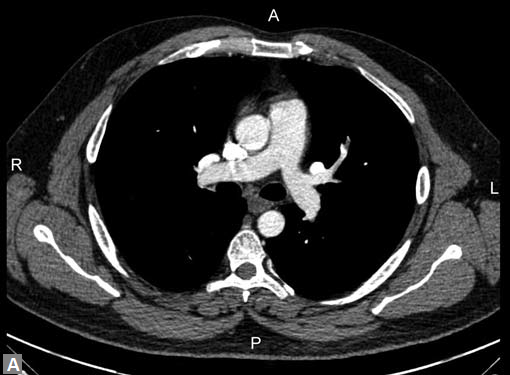

Aorta11 has five segments namely: (1) root, (2) ascending aorta, (3) proximal aortic arch, (4) distal aortic arch and (5) descending thoracic aorta. Size and shape of aorta vary among individuals and with age in an individual. Aortic root includes annulus, valve and sinuses of Valsalva. Average diameter at the level of sinotubular junction is 36 mm. Ascending aorta extends from sinotubular junction to the level of origin of innominate artery. Average diameter in adult is 35 mm. The aortic arch extends from the origin of right innominate artery to origin of left subclavian artery. Isthmus extends from left subclavian artery to the level of ligamentum arteriosum and is slightly narrower than adjoining descending thoracic aorta, particularly in infants. Most cranial part of descending thoracic aorta is more prominent than rest of descending thoracic aorta and is known as aortic spindle, more commonly appreciated in children. Average luminal caliber of mid thoracic aorta is 25 mm. Distal descending thoracic aorta just above diaphragm has an average of 24 mm.

Connective tissue disease, hypertension and iatrogenic (Figs 19K to L) injury are the common causes for dissection. Radiologist not only establishes the diagnosis, also evaluates the extent of dissection, presence of thrombosis particularly in false lumen. In case of type A dissection, involvement of aortic root is determined. Relation of thrombosed lumen and ostia of coronary vessels, cephalad branches (Figs 19N, R to V) of aorta is determined. Most of the occasions membrane is demonstrated. Spiral nature of the membrane can be seen

Tennis ball sign is the classical appearance of dissection on

transverse section.

Double barrel appearance is seen on coronal and sagittal

images. Type B dissections can extend even to common

iliac arteries bilaterally. Superiorly it can extend to involve

common carotid and vertebral arteries.

Motion artifacts12 particularly in aortic root and ascending

aorta can masquerade a dissection.

To avoid these artifacts and make interpretation accurate

retrospective gating should be employed. Pseudolumen

generally enhances late compared to true lumen and

this should not be misinterpreted as thrombus. Delayed

second phase reveals the filling of pseudolumen if it is not

thrombosed. Occlusion of major vessels arising from the

thrombosed pseudolumen can result in ischemia/infarction

of organs/structures supplied by these vessels. Pain in loin

due to renal infarct may be presenting feature of a dissection.

Pericardial effusion may accompany type A dissection.